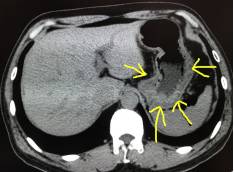

如上圖1:黃色箭頭指的就是胃,這是一個(gè)沒有喝水,沒有充盈好的胃,我們可以看到箭頭指的胃壁是明顯厚的,正常的胃壁也是厚的,但是如果里面隱藏了著東西,剛好胃壁這里有個(gè)小胃癌,那就沒辦法診斷了,就會導(dǎo)致漏診。